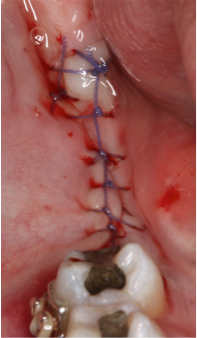

Fig 6 e 7 Posicionamento final dos implantes e sutura